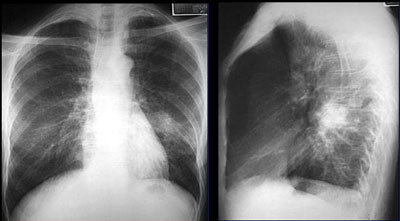

Для того чтобы выявить заболевание легких, практически во всех случаях выполняют комплекс обследований, результаты которых оценивает опытный пульмонолог. Если у пациента была выявлена мелкоочаговая пневмония, то так называемая рентгенологическая картина становится вариабельной. При помощи рентгенографии специалисты определяют произошедшие изменения на фоне инфильтрации. В наиболее сомнительных случаях данные обследования уточнят с помощью МРТ легких.